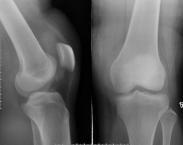

關節損傷簡介:關節是由關節囊、關節面和關節腔構成。當關節遭遇外傷或暴力作用是會導致關節損傷,出現關節脫位、韌帶損傷等等。

• 脛骨平臺骨折

628健康網為您分享有關脛骨平臺骨折的癥狀,脛骨平臺骨折的治療方法,脛骨平臺骨折的預防知識,脛骨平臺骨折的癥狀圖片,脛...

• 骨關節病

628健康網為您分享有關骨關節病的癥狀,骨關節病的治療方法,骨關節病的預防知識,骨關節病的癥狀圖片,骨關節病吃什么藥,骨...